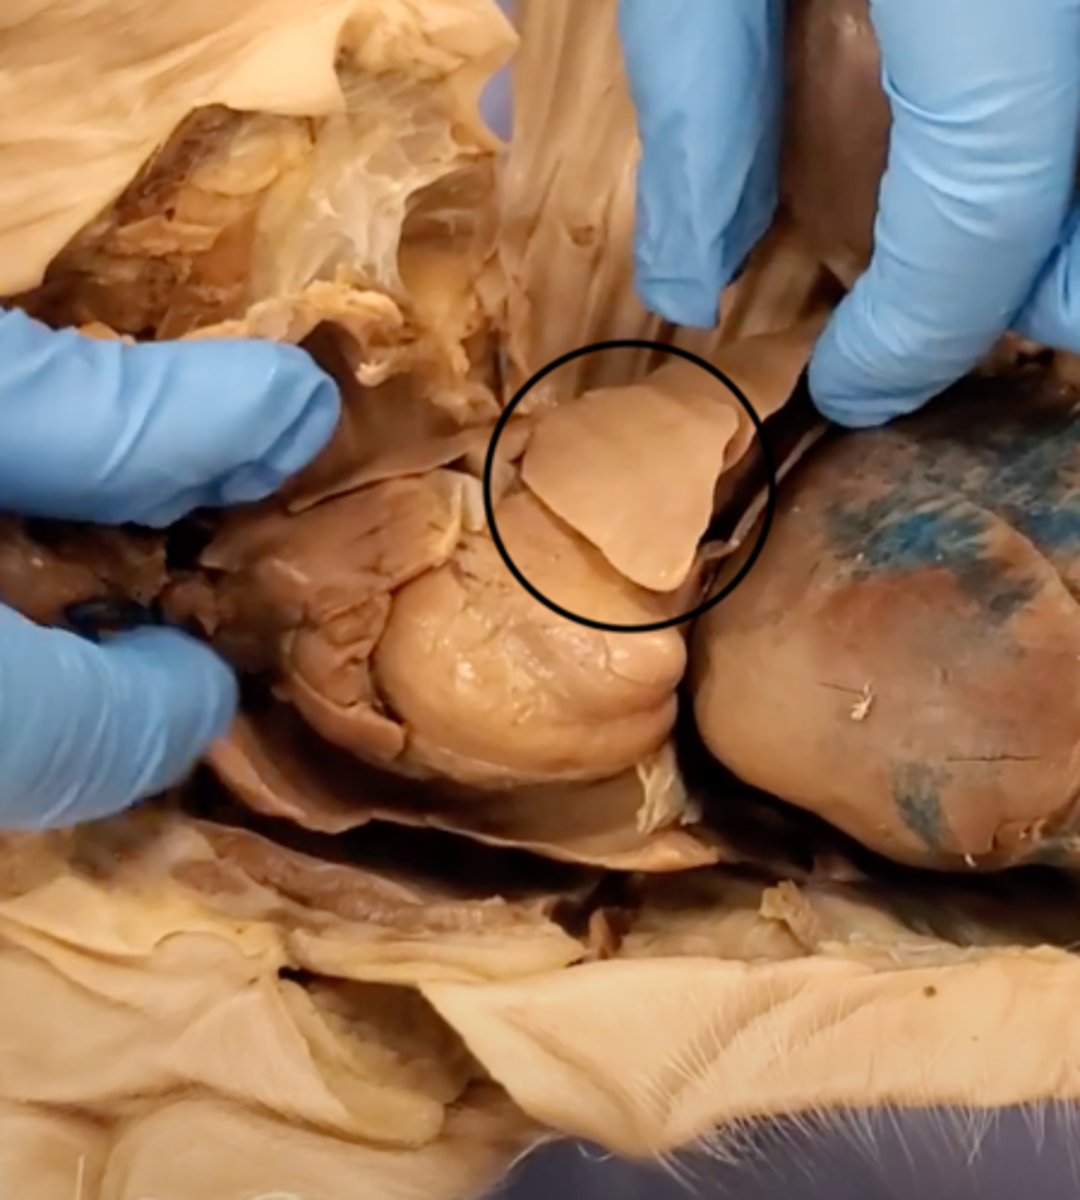

Tricuspid Valve (Right Atrioventricular Valve)

1-valve

Bicuspid valve (Left Atrioventricular Valve)

2-valve

Pulmonary Semilunar Valve

3-valve

Aortic Semilunar Valve

4-valve

pulmonary trunk (model)

yellow sash of fat that tells you this if the front side of the heart (model)

t-shaped ribbon of fat on back side of heart (model)

Left ventricle (model)

has the most muscle mass because it has to pump blood to the whole body

apex (model)

base (model)

where everything connects

yellow sash of fat that tells you this if the front side of the heart (dissection)

pulmonary trunk (dissection)

t-shaped ribbon of fat on back side of heart (dissection)

left auricle (dissection)

right auricle (dissection)

left ventricle (dissection)

right ventricle (dissection)

right atrium (dissection)

left atrium (dissection)